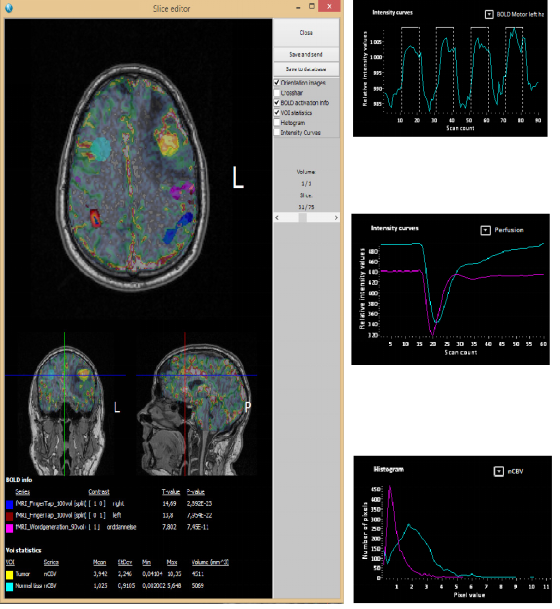

NordicBrainEx是專爲臨床設計的fMRI後處理軟件。簡易而功能強大的界面提高瞭(le)用戶的工作效率。先進的感興趣體積工具、BOLD激活區域的2D/3D可視化、DTI纖維追蹤成像和灌注MRI圖讓臨床醫生可對病竈周圍區域的大腦組織進行廣泛且深入的評估。(對於(yú)腫瘤的分類,分級,術中導航以及治療後的跟蹤監測有重要作用)

5.創(chuàng)建感興趣體積提取量化參(cān)數值,信号強度曲線和直方圖。

6.利用感興趣體積分離DTI纖維組、BOLD fMRI 區域或感興趣腦血流區域體積。保存並(bìng)發送到PACS或與結構像融合讓第三方的臨床方案和神經導(dǎo)航系統可以使用。

可視化交互測量